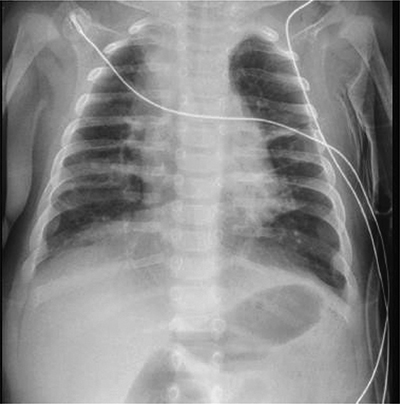

At 14 weeks of corrected age, the patient developed an episode of bronchiolitis. Thoracic radiography showed multiple pulmonary opacities and an air bronchogram suggesting pneumonia (Figure 1), treated with antibiotics, and abdominal radiography showed hyperinflation (Figure 2).

Figure 1

Chest antero-posterior radiograph.

Multiple pulmonary opacities and an air bronchogram suggesting pneumonia.